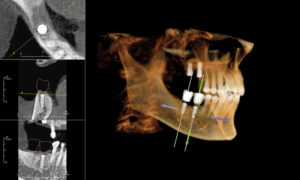

Our centre utilizes state-of-the-art 3D cone-beam CT (computed tomography) technology that provides highly accurate 3-D radiographic images for the diagnosis, planning and treatment of oral surgery.

This technology provides highly accurate 3D radiographic images for the diagnosis, planning and treatment of dental implantology, TMJ analysis, airway assessment, oral and orthognathic surgery and other dental procedures.

Undistorted, anatomically correct views of the jaws, teeth and facial bones along with cross-sectional (bucco-lingual), axial, coronal, sagittal, cephalometric and panoramic views are easily generated.